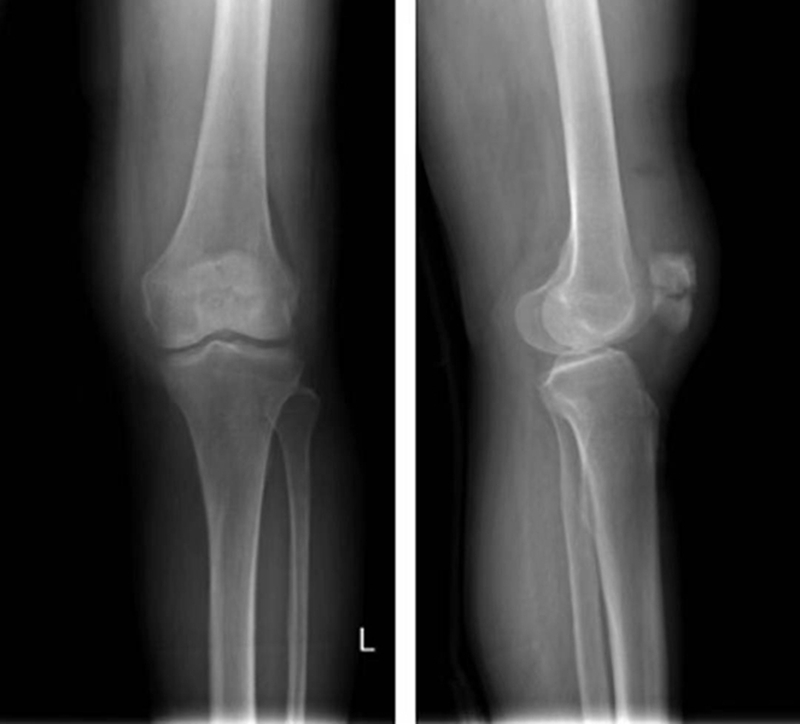

正常髌骨中心点应位于下肢轴线上或稍内侧(图1)。对于髌骨不稳定,膝关节正位像可见髌骨偏离正常的位置,向外侧移位(图2、图3)。

图2 膝关节正位X线成像显示了双侧髌骨偏离正常的解剖位置,明显向外侧移位